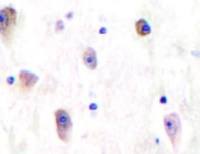

Staining of human peripheral blood platelets with Rat anti Human CD49f:Biotin

Staining of human peripheral blood lymphocytes with Rat anti Human CD49f:Biotin